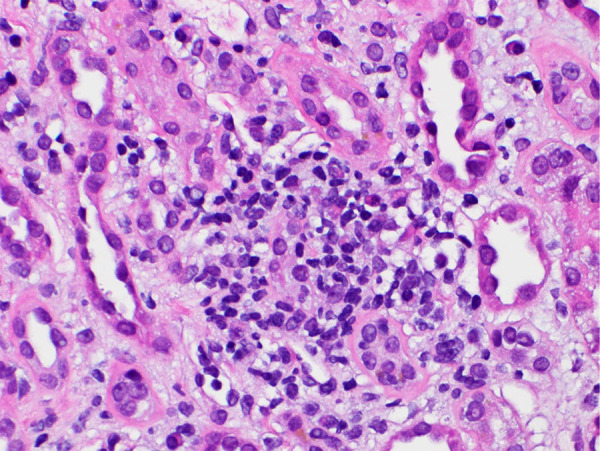

急性间质性肾炎(AIN)是医院获得性急性肾损伤(AKI)的常见病因[1]。AIN最常见的病因是药物诱发的AIN,占60-70%的病例[2]。阿利昔单抗(PCSK9 抑制剂)是一种单克隆抗体,通过抑制 PCSK9 蛋白降低低密度脂蛋白-C 水平[3]。阿利库单抗常见的不良反应包括注射部位反应、肌痛、神经认知障碍和眼科疾病 [4]。有关阿利珠单抗引起急性肾小管坏死(ATN)的病例报道较少,且多以急性肾小管坏死的形式出现[5]。本文介绍了一例与阿利珠单抗使用相关的 AIN 新病例。

Acute interstitial nephritis (AIN) is a common cause of hospital-acquired acute kidney injury (AKI) [1]. The most common cause of AIN is drug-induced AIN, which accounts for 60 - 70% of cases [2]. Alirocumab, a proprotein convertase subtilisin/kexin type 9 inhibitor (PCSK9 inhibitor) is a monoclonal antibody that lowers low-density lipoprotein-C levels by inhibiting the PCSK9 protein [3]. Common adverse events reported with alirocumab include injection-site reactions, myalgia, neurocognitive disorders, and ophthalmologic disorders [4]. There is paucity of data, with few reported cases of AKI, mostly in the form of acute tubular necrosis (ATN) associated with alirocumab [5]. In this article, we present a novel case of AIN associated with the use of alirocumab.